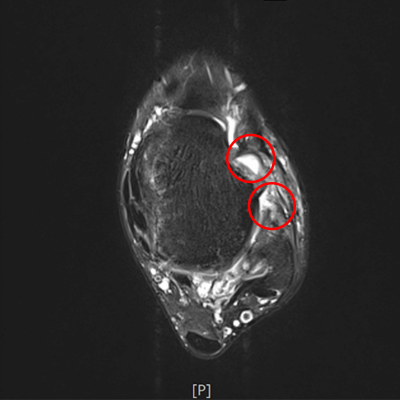

발목인대파열 수술 전

발목인대 부착부의 파열과 전반적인 파열 및 퇴행

2019.12.21

발목인대파열 수술 후

지지대를 보강하여 재건함